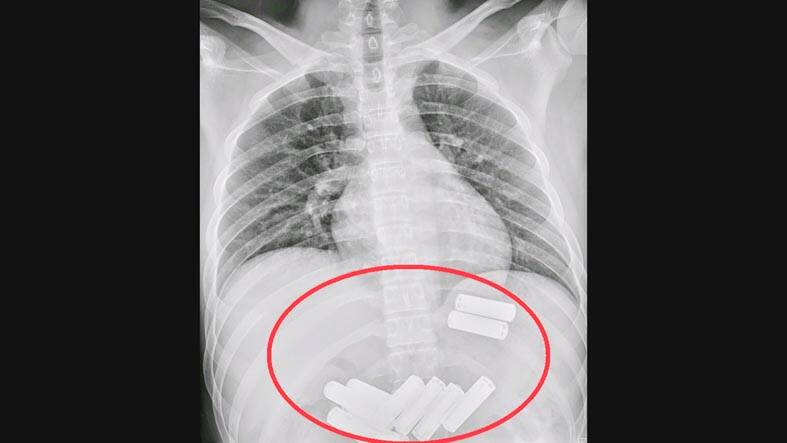

From an X-ray, doctors confirmed the presence of 11 AA batteries in Lee’s stomach, he said.

Photo courtesy of Da Chien General Hospital via CNA

When conducting a gastroscopy, using an endoscope to examine the upper digestive tract, they also discovered a lot of food among the batteries, he added.